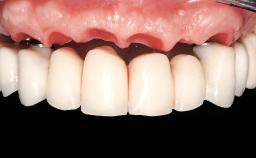

Immediate Loading of Eight Implants in the Maxilla and Six Implants in the Mandible and Final Restoration with Three-Unit and Four-Unit FDPs

Prosthesis Type FDP

SAC Level Complex

Defining Characteristics Fully edentulous upper jaw to be rehabilitated with an implant-borne fixed dental prosthesis

Loading Protocol Immediate

Retention Cemented, with prosthesis margin < 3mm submucosal Cemented, with prosthesis margin < 3mm submucosal